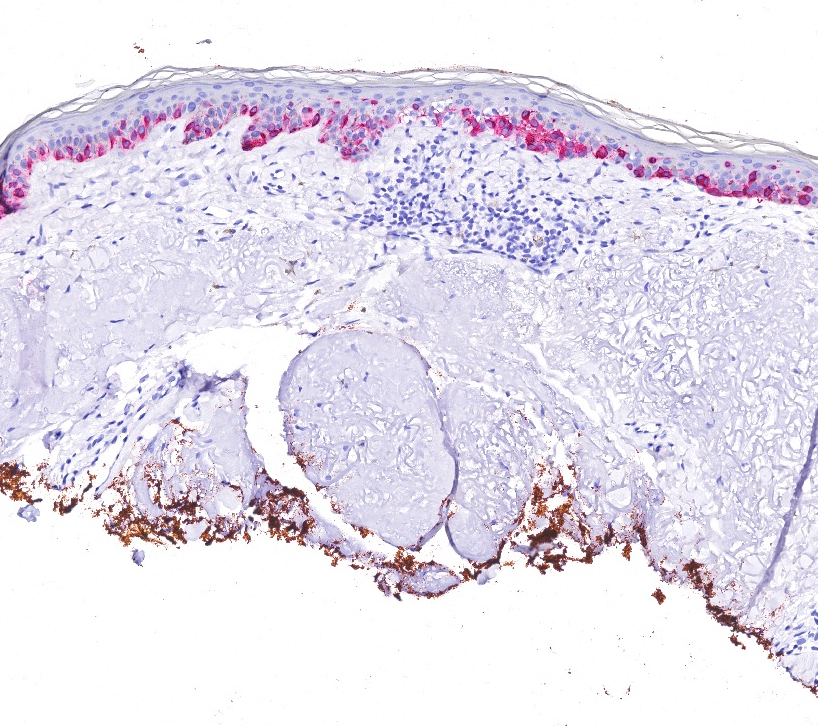

Positive stains

- Immunohistochemistry for MelanA / MART1, SOX10 and MITF may assist in diagnosis by highlighting the arrangement of melanocytes in the epidermis and by assisting in identification of dermally invasive cells (Am J Dermatopathol 2014;36:387, Am J Dermatopathol 2014;36:124)

- Involvement of adnexal epithelium

Microscopic (histologic) images

Contributed by Joseph Gillam, M.D., Jennifer Crimmins, M.D. and Mark Mochel, M.D.